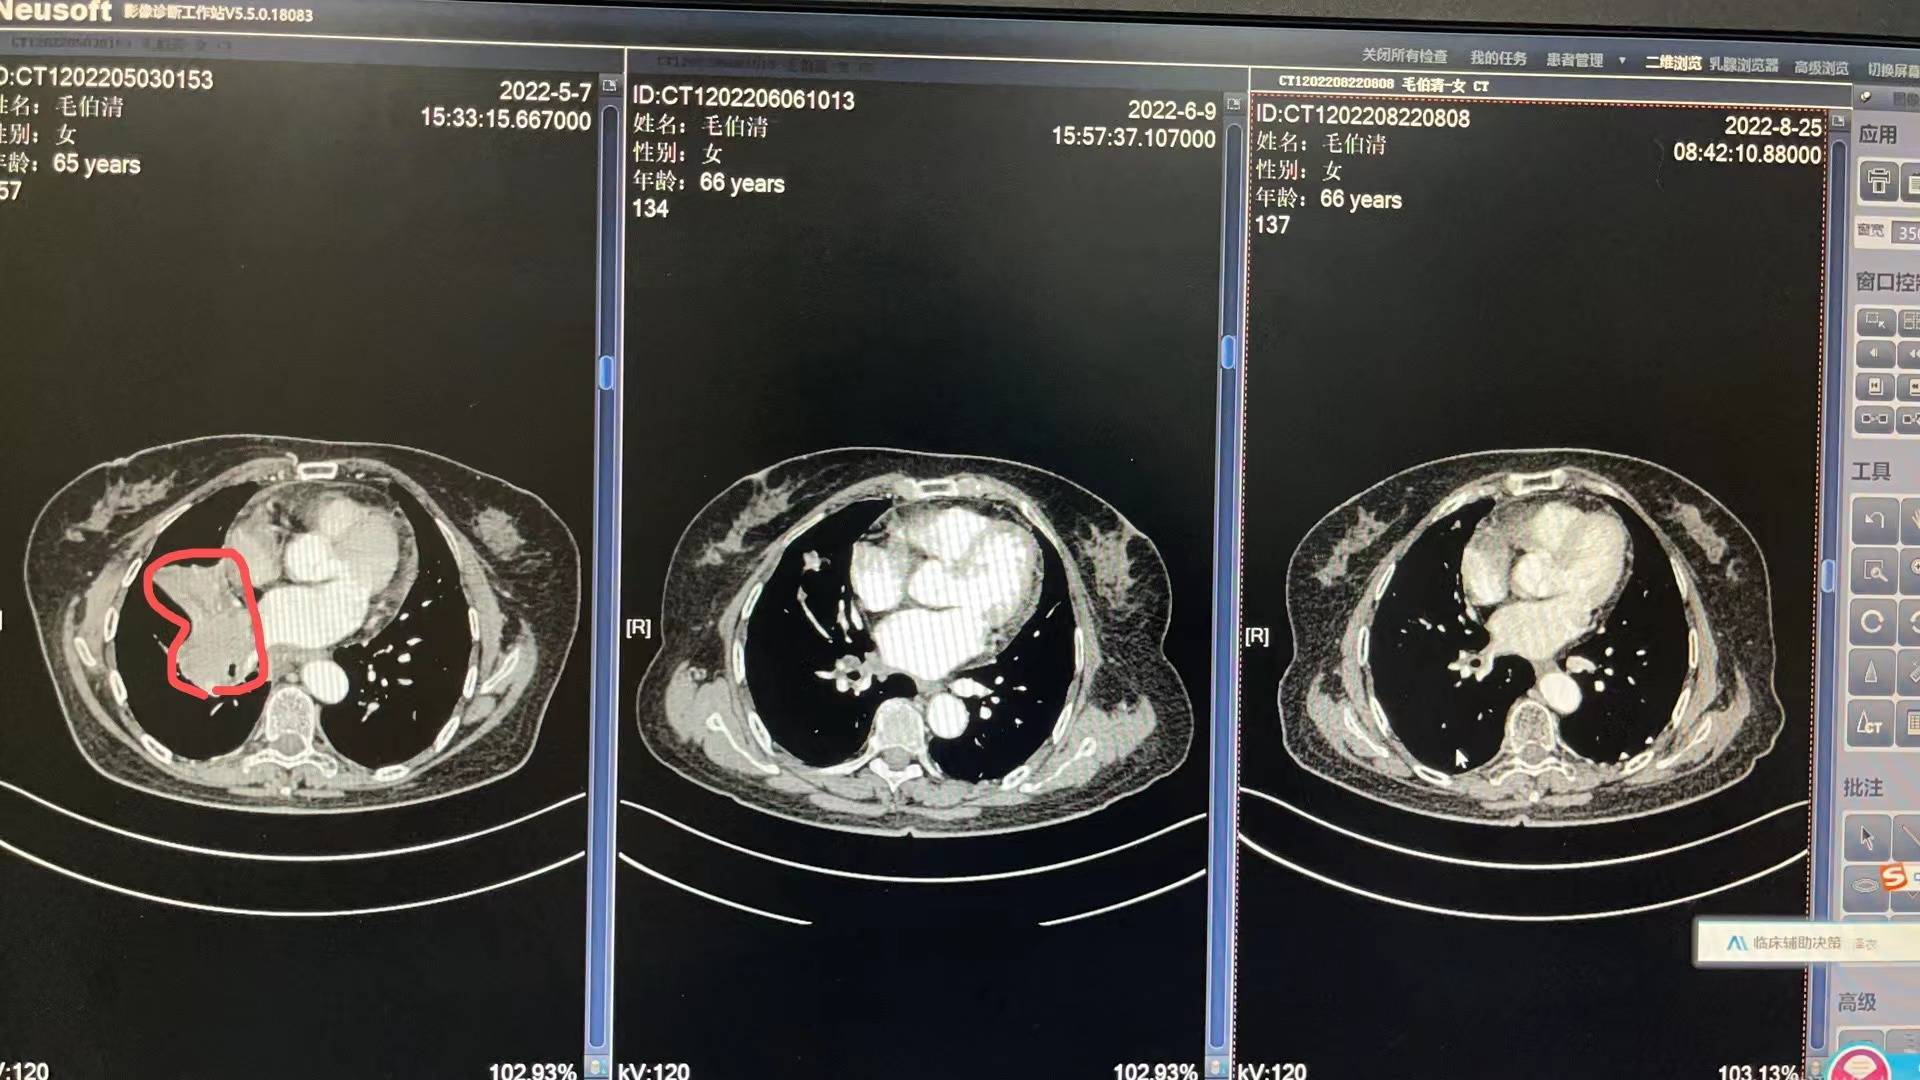

5月3号妈妈入院开始各种检查流程,5月13号病理出来,没有逃过此劫,确诊小细胞肺癌T4N2M0 IIIc期 局限期。妈妈的肿瘤是比较大的,5月14号上治疗,依托铂苷+顺铂,第二次化疗是6月6号,第三次化疗是6月29号,都是化疗三天出院,打升白针,便秘严重,喝乳果糖没啥用,两三天后自然好转。医生开了中药饮片以及一些药出院,刚化疗完那几天妈妈状态很不好,没力气,没精神,喜安静,但是可以下床吃饭,大部分时间躺床上睡觉。食欲不是很好,给她熬的瘦肉粥。四五天后状态开始慢慢好转!7月11号开始放疗,期间停掉第四次化疗,医生说怕身体承受不住,我妈是1天2次,15天完成,20次放疗后出现吞咽有哽咽感,医生只开了一瓶康复新液,就没喝了,7月底放疗结束后,慢慢哽咽感减退,医生让我妈妈回家休息一个把月。

每次她的血常规和肝肾功能都比较不错,有一点贫血的迹象,医生让吃点猪肝和血旺!她的白细胞和血小板都在往下掉,虽然都还在正常值范围内,医生说不错,可是我有一些些紧张!因为妈妈还有三次化疗。前天我妈妈去做了一个胸部复查,她的肿瘤基本没有了,其实在她第二次化疗后复查,肿瘤就小了很多,这次结果医生说还有些残留。准备这次入院化疗给她做一个胸部pet,看看残留的性质是不是活性,如果不是,就表示影像完全没有了。

附上医生给我截图的影像图和复查报告,请比我懂得多,比我专业的朋友帮忙看看!